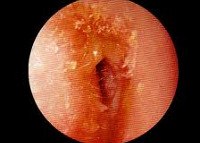

При развитии симптомов среднего отита следует обратиться к врачу. Врач осмотрит ухо с помощью отоскопа, проверит, воспалена ли барабанная перепонка и нет ли скоплений гноя в среднем ухе. Возможно будет назначен курс пероральных антибиотиков и анальгетики , чтобы облегчить боль. В большинстве случаев боль утихает через несколько дней, но небольшая потеря слуха может иногда наблюдаться еще неделю или более. Если отит осложнился холестеатомой, обычно возникает необходимость в ее удалении хирургическим путем.

Если из уха ребенка выделяется гной или боль в ухе продолжается более нескольких часов, следует обратиться к врачу. Он осмотрит уши ребенка, возможно, подует в них из специального инструмента, чтобы определить, нормально ли двигается барабанная перепонка.

В зависимости от возраста ребенка могут быть проведены самые различные слуховые тесты, выявляющие, нарушение слуха и степень расстройства. Специалист может выполнить тест, при котором при помощи инструмента в ухо направляются струи воздуха. Этот тест измеряет количество движений барабанной перепонки (при среднем отите оно гораздо меньше). Поскольку заболевание протекает нестабильно, врач может назначить повторные тесты через 3 месяца.